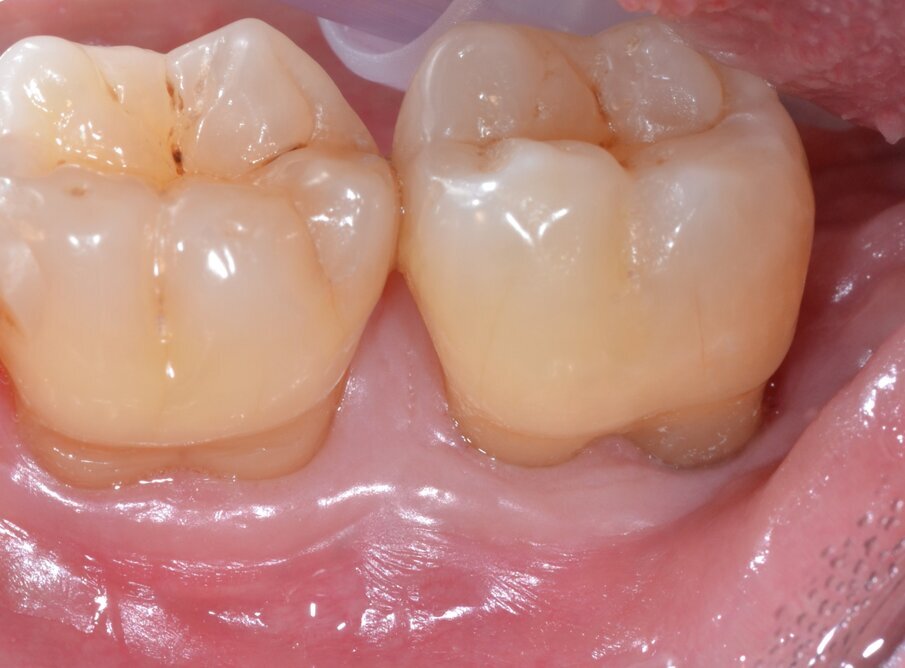

A distanza di 12 e 24 mesi il paziente viene richiamato per un controllo radiografico dell’elemento dentario trattato e vengono nuovamente effettuate le misurazioni dei valori di PPD, CAL e BoP (Figg. 13-15).

ig. 13 - Aspetto dei tessuti parodontali a guarigione avvenuta (follow-up a 24 mesi).

Fig. 15 - RX postoperatoria che evidenzia la completa rigenerazione del difetto osseo (follow-up a 24 mesi).

Alla baseline il valore di PPD nell’area interessata dal difetto intraosseo era pari a 8,5 mm con un indice di BoP+ mentre al momento dell’ultimo controllo (24 mesi) il valore medio di PPD era pari a 2,5 mm con un indice di BoP- con una riduzione media del valore di PPD pari a 6,0 mm. Gli esami radiografici, effettuati per mezzo di radiografie endorali periapicali, hanno confermato un sostanziale riempimento del difetto intraosseo.